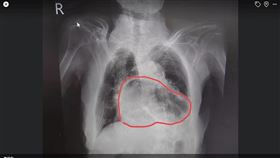

車禍撞破橫膈膜 胃卡肺部及時獲救

一名男子車禍撞擊腹部造成罕見的橫膈膜破裂,整個胃部移...